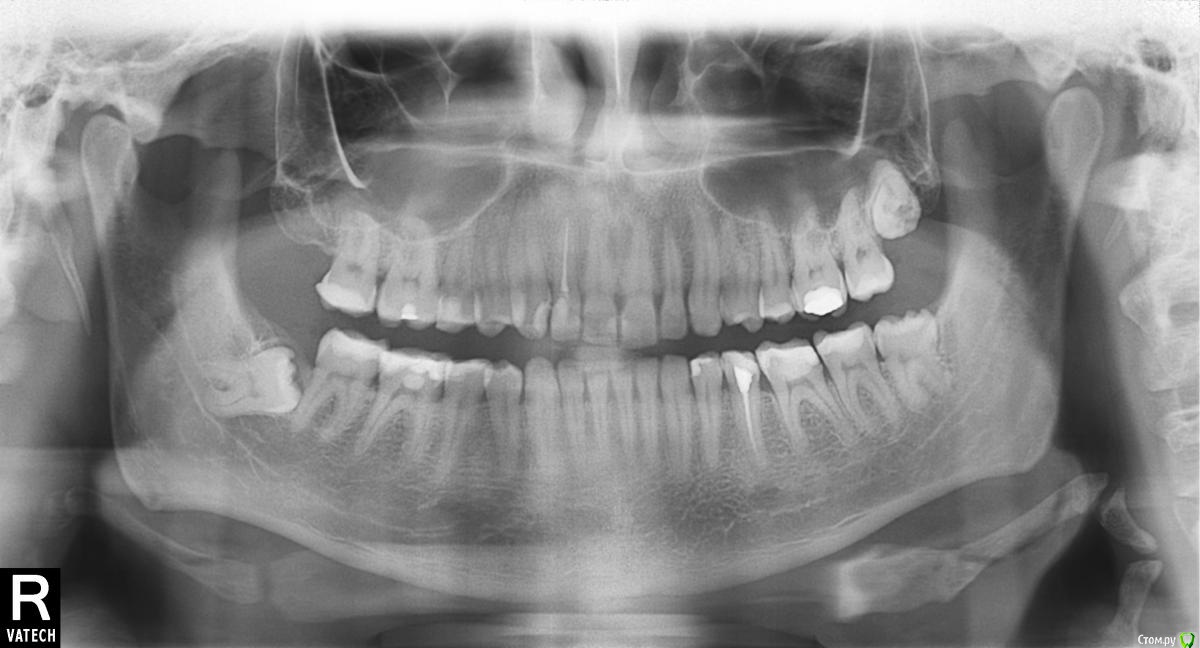

dm_Consul Опубликовано 31 октября, 2016 Автор Поделиться Опубликовано 31 октября, 2016 КТ с ВНЧС сделал, а к ортодонту только 22-го ноября попаду(очередь). Есть ли смысл сходить ещё к какому-нибудь врачу пока приём жду? Например к челюстно-лицевому хирургу. Возможно он какие-то временные облегчающие меры для сустава посоветует...Просто до приёма ортодонта долго, боюсь как бы чего не развалилось у меня, или не произошло непоправимого, щёлканья жутко на нервы действуют Ещё вопрос интересует. На своей ортопонараме я явно вижу что у меня как то челюсть перекошена, то есть с одной стороны край кости ниже намного чем с другой. Указал зелёной линией. В реальной жизни я это никак не замечаю. Это опасно? Это что-то врожденное или это как раз из-за глубокого прикуса так сместилось? Ссылка на комментарий